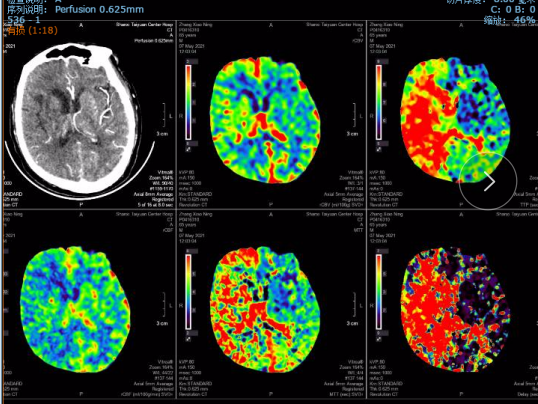

CTP:

右侧基底节区、颞叶、顶叶低灌注区域。

此患者临床症状为右侧大脑中动脉闭塞导致的缺血表现,左侧肢体偏瘫、语言不流利、反应迟钝,临床症状很重,mRs评分5分,生活不能自理。但是头颅CT表现却不是整个右侧半球的大面积梗死,脑血管造影提示右侧大脑中动脉的额干和颞干均闭塞,虽然通过大脑前动脉和大脑后动脉的软膜吻合有一定代偿,但代偿不足,脑灌注提示右侧半球明显低灌注。提示虽然右侧大脑中动脉闭塞,但是其支配区域仍然有一定体积的处于低灌注目前尚未完全坏死的脑组织,符合《2018症状性动脉粥样硬化性非急性颅内大动脉闭塞血管内治疗中国专家共识》推荐意见,适合血管内再通治疗。当然也可以选择颅内外血管搭桥治疗,经过和家属充分沟通后,决定选择血管内再通治疗。拟于2021-4-28在全麻下进行血管内再通手术。

术后8天头颅CT及CTP影像:无出血,右侧半球脑灌注较术前明显改善。